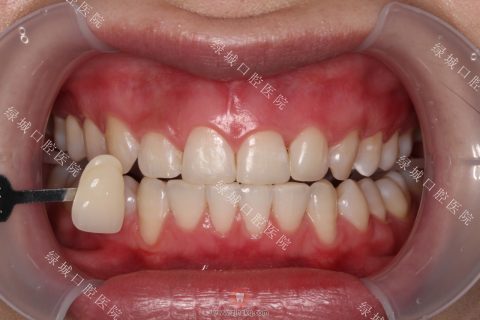

3、效果好吗?

大家最期待的一定是冷光美白的效果。用事实说话,这是我们冷光美白前后的对比,牙色在一定程度上变白,患者也比较满意。

冷光美白后